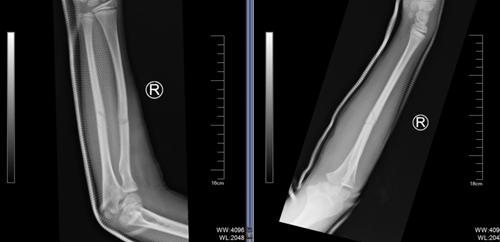

03 病例三

還有一名 10 歲男孩踢球時(shí)摔傷了右前臂,因腫脹疼痛無法活動(dòng),同樣來到了青島市婦女兒童醫(yī)院兒童骨折整復(fù)門診,尋求手法復(fù)位的幫助。經(jīng)門診醫(yī)生仔細(xì)評(píng)估,認(rèn)為孩子符合手法復(fù)位的條件,最終通過嫻熟的手法完成。這些孩子都成功避免了手術(shù),在無創(chuàng)治療下恢復(fù)了健康。

復(fù)位前

復(fù)位后